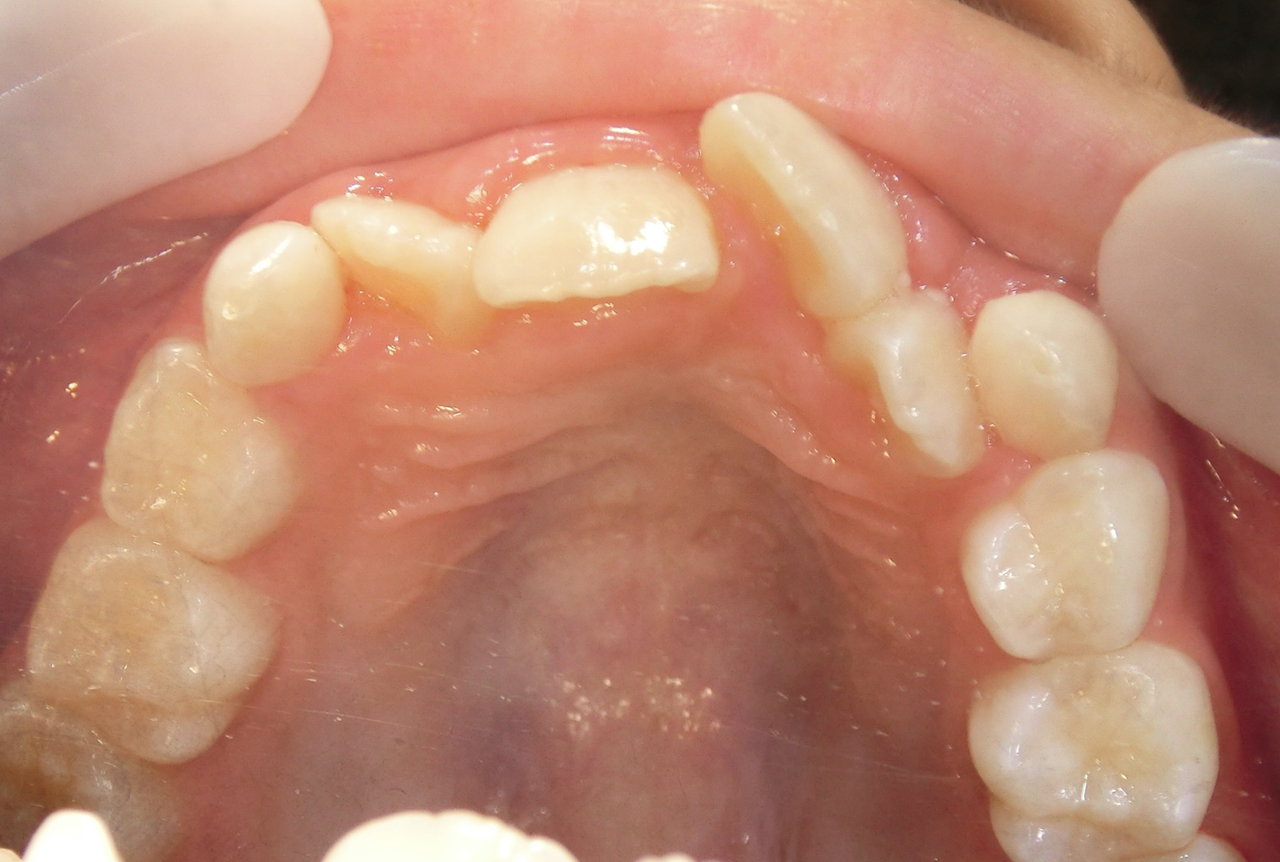

治療前

治療説明 歯科矯正で取り外し可能な矯正方法である床矯正で治療しました

治療期間 2年1か月

治療費200000 円

治療後

治療の副作用(リスク)歯の動き方には個人差があり、予想された治療期間が延長する可能性があります。。床矯正の使用状況、矯正歯科治療には患者さんの協力が必要であり、それらが治療結果や治療期間に影響します。2次矯正が必要になる場合もあります。